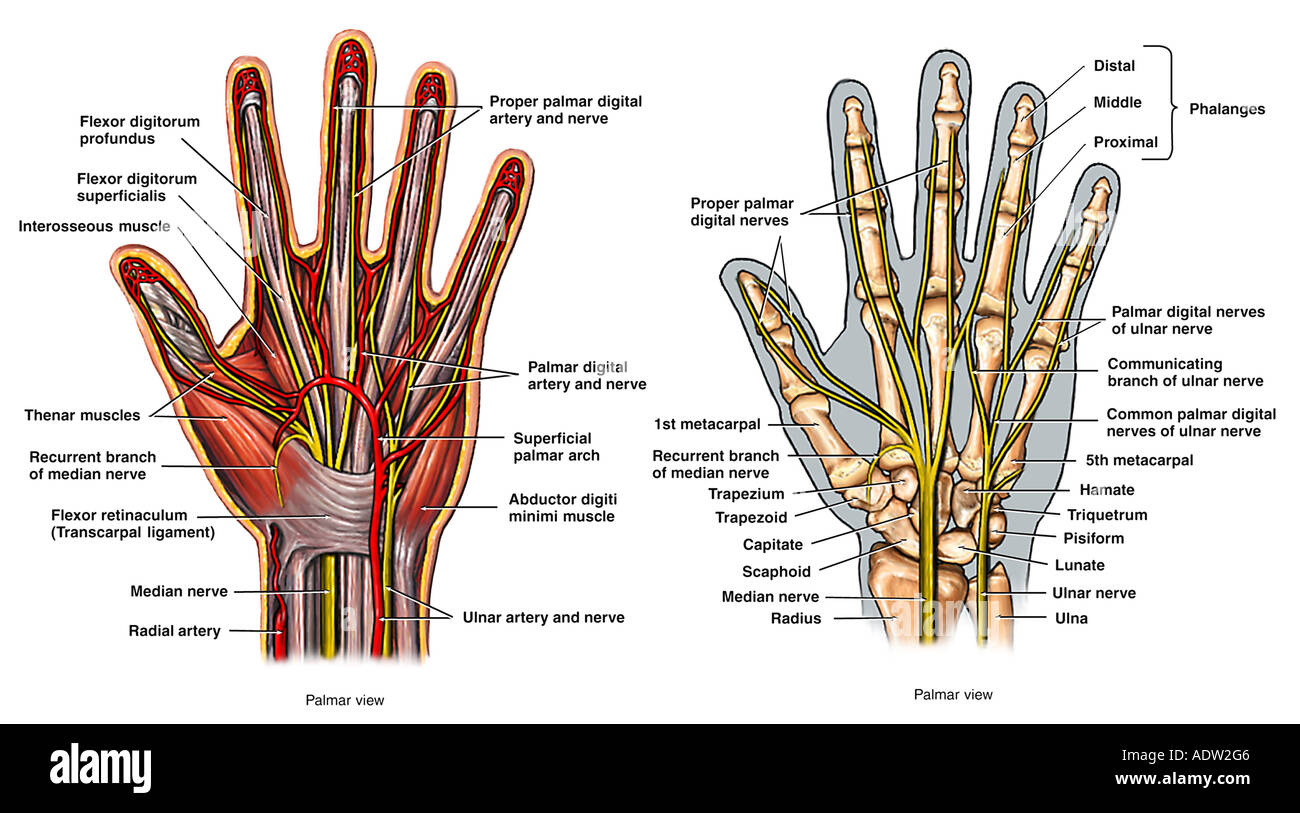

Anatomía de la mano humana ilustración Fotografía de stock Alamy

el cuerpo humano y sus partes MUSCULOS DE LA MANO

Anatomía de la mano humana, la ilustración Fotografía de stock Alamy

Anatomía de la mano humana Fotografía de stock Alamy

Anatomía de la mano humana Fotografía de stock Alamy